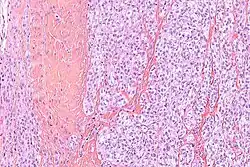

Makroskopowo guz stanowi drobnoguzkową lub zrazikową spoistą masę ściśle związaną ze ścięgnem, rozcięgnem lub powięzią, koloru szarobiałego[10]. Na przekroju mogą być obecne ogniska martwicy, krwotoków lub zwyrodnienia torbielowatego[2][9]. Rzadko mogą być obecne brązowe lub czarne ogniska odpowiadające nagromadzeniu melaniny[2].

W obrazie mikroskopowym utkanie guza tworzą gęste gniazda lub pęczki komórek wrzecionowatych lub poligonalnych pooddzielane przegrodami łącznotkankowymi. Komórki o wrzecionowatym lub wielobocznym kształcie są wyraźnie odgraniczone, posiadają obfitą jasną lub słabo eozynofilną cytoplazmę z pęcherzykowym jądrem i wydatnym bazofilnym jąderkiem[2][9]. Aktywność mitotyczna jest niska, podobnie stopień pleomorfizmu jest niewielki. W około połowie guzów obecne są wielojądrowe komórki olbrzymie oraz ogniska melaniny[2].